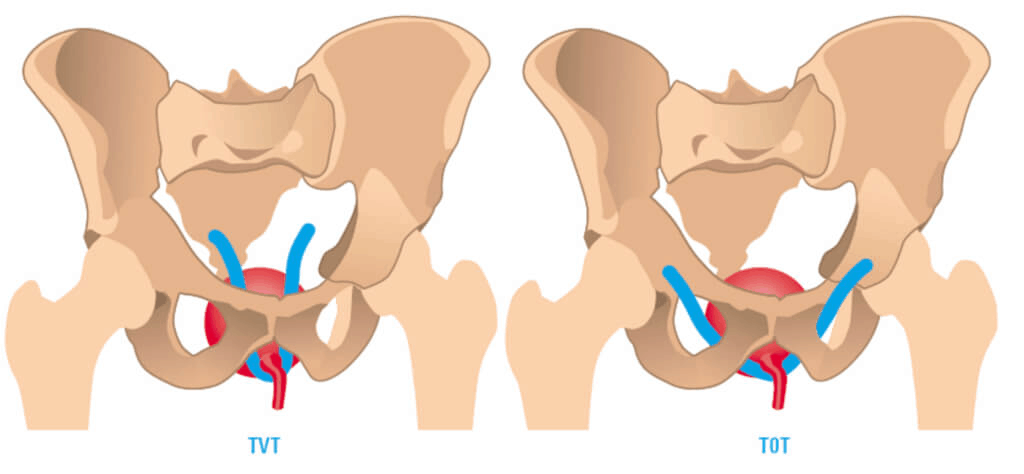

2. Surgical treatment is certainly the most effective method of treatment and involves the placement of synthetic mesh so-called slings, transopturative tape (TOT)

The meaning of surgical intervention in resolving stress urinary incontinence is the restitution of the normal position and support of the vesicourethral segment, which usually leads to the solution of this problem.

The operation itself is very safe, short one and can be performed under all types of anesthesia. The success of resolving stress urinary incontinence with these surgical techniques is very high and is around 90%!

Given that the transobturator approach has a minimal number of surgical complications, it is to be expected that it occupies a leading position in the surgical treatment of stress urinary incontinence.

TOT gold standard in the treatment of female stress urinary incontinence – SUI